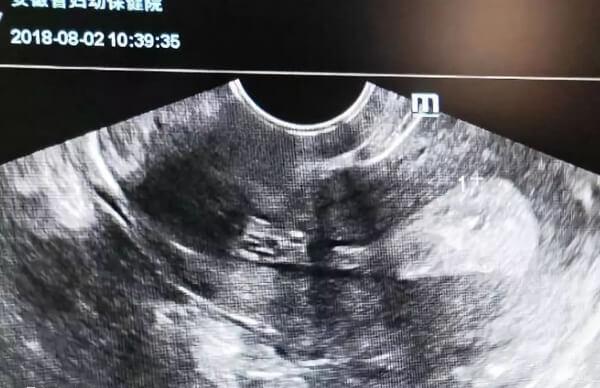

影响体外受精胚胎着床的因素有很多,子宫环境是一个关键点。在进入体外受精周期之前,患者朋友可以抓紧时间调整身体,补充一些有助于子宫维护的食物,注意个人清洁和卫生,避免子宫内膜炎症。